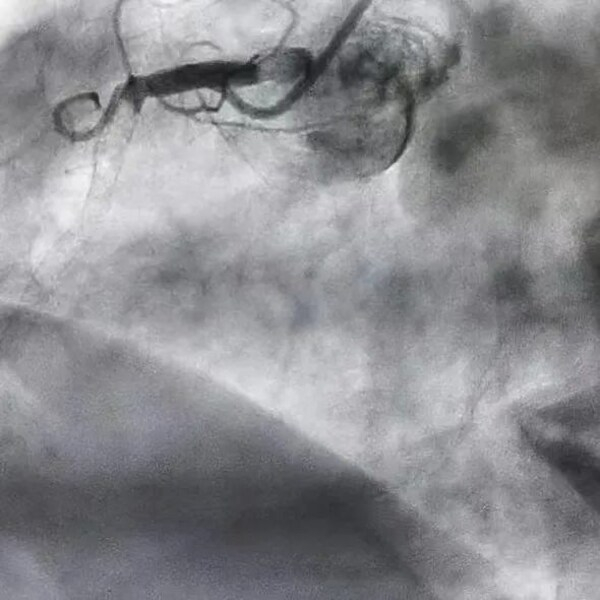

近日,上海德达医院葛均波院士团队抢救了一位新冠病毒感染7天,支架内血栓导致急性心梗的患者。经过急诊手术,从堵塞的右冠抽出巨大血栓,心脏动脉血流恢复正常,患者转危为安。

手术前